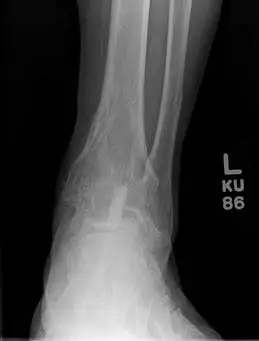

This is a series of pics of an ankle fusion takedown with replacement with a total ankle implant.  The patient was having pain and getting arthritic changes at the talonavicular joint. This is the first ankle fusion takedown with replacement of a total ankle implant performed in South Florida by one of the surgeons in our practice.

These are pics of the fusion prior to takedown

These first three pics are placement of screws in the medial malleolus and distal fibula to aid in stability.